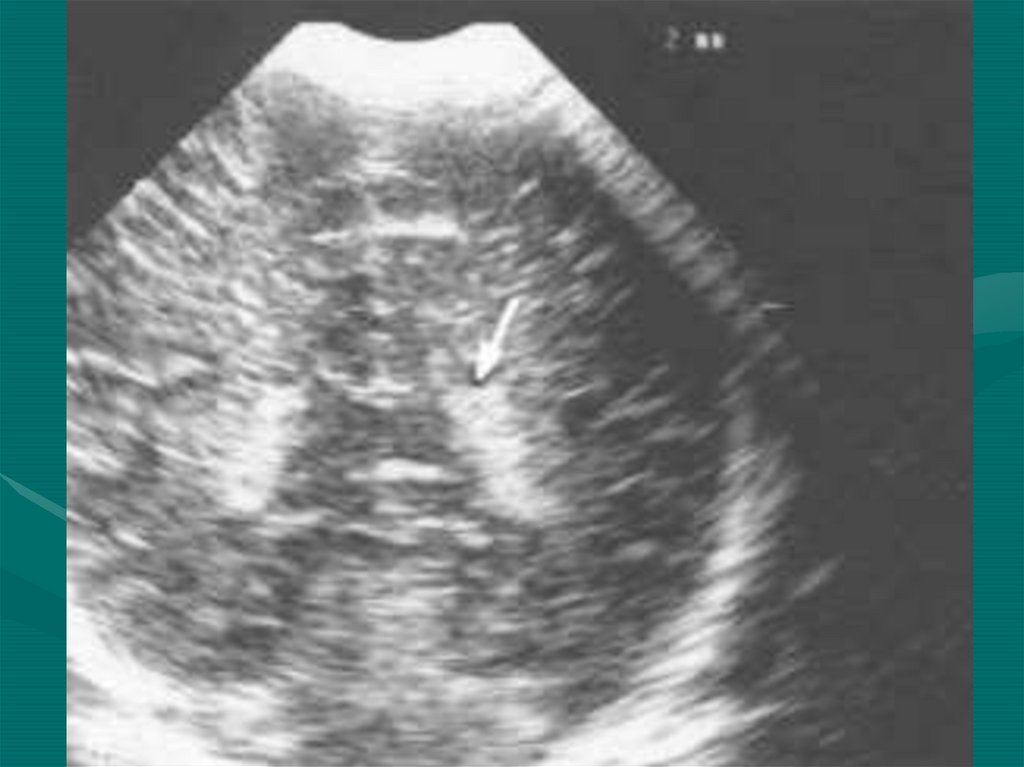

17. Ультразвуковая группа

• Эхоэнцефалография (ЭхоЭГ)

• Ультразвуковая допплерография (УЗДГ)

• Двойная ультразвуковая допплерография

• Транскраниальная допплерография

• Нейросонография